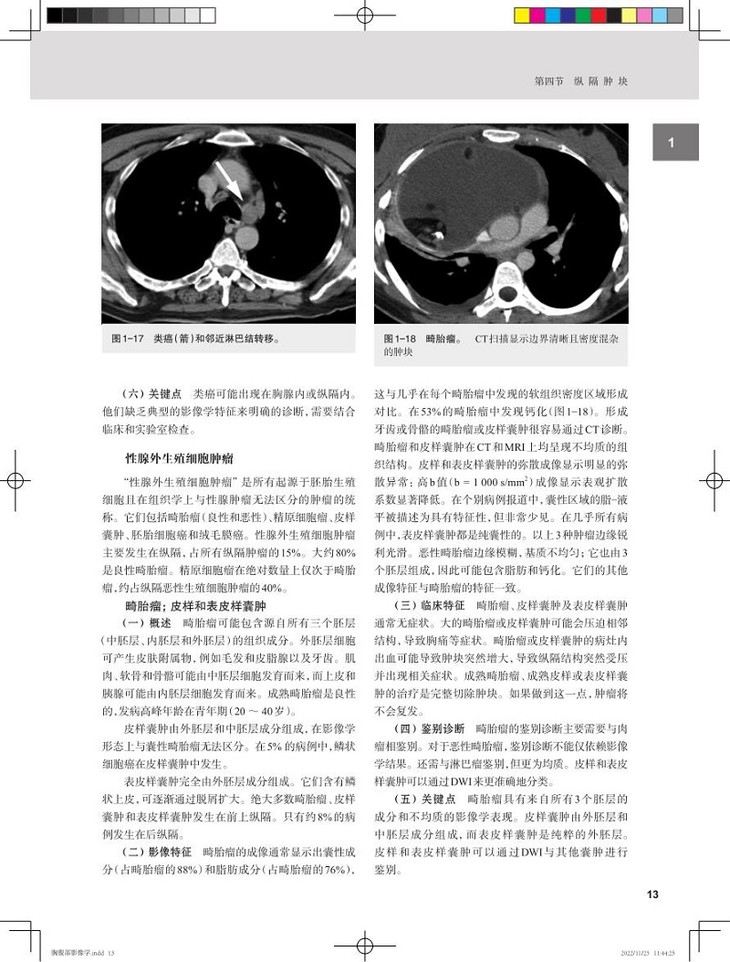

本书是一部精练的胸腹部影像医学精要,内容分为两大部分,第一部分胸部,包括纵隔、心脏和心包、大血管、肺和胸膜4 章;第二部分腹部,包括肝脏、胆囊和胆道、胰腺、消化道、脾和淋巴系统、肾上腺、肾脏和尿道、女性盆腔、男性盆腔9章,每种疾病都从定义、影像征象、临床特征、鉴别诊断和关键点等角度进行阐述,特别强调临床表现、解剖标志与影像表现结合的读图方法,指出每种疾病首shou选检查方法及各种检查方法优缺点,并对重点内容进行了提炼,以“提醒”“警惕”单独列出。